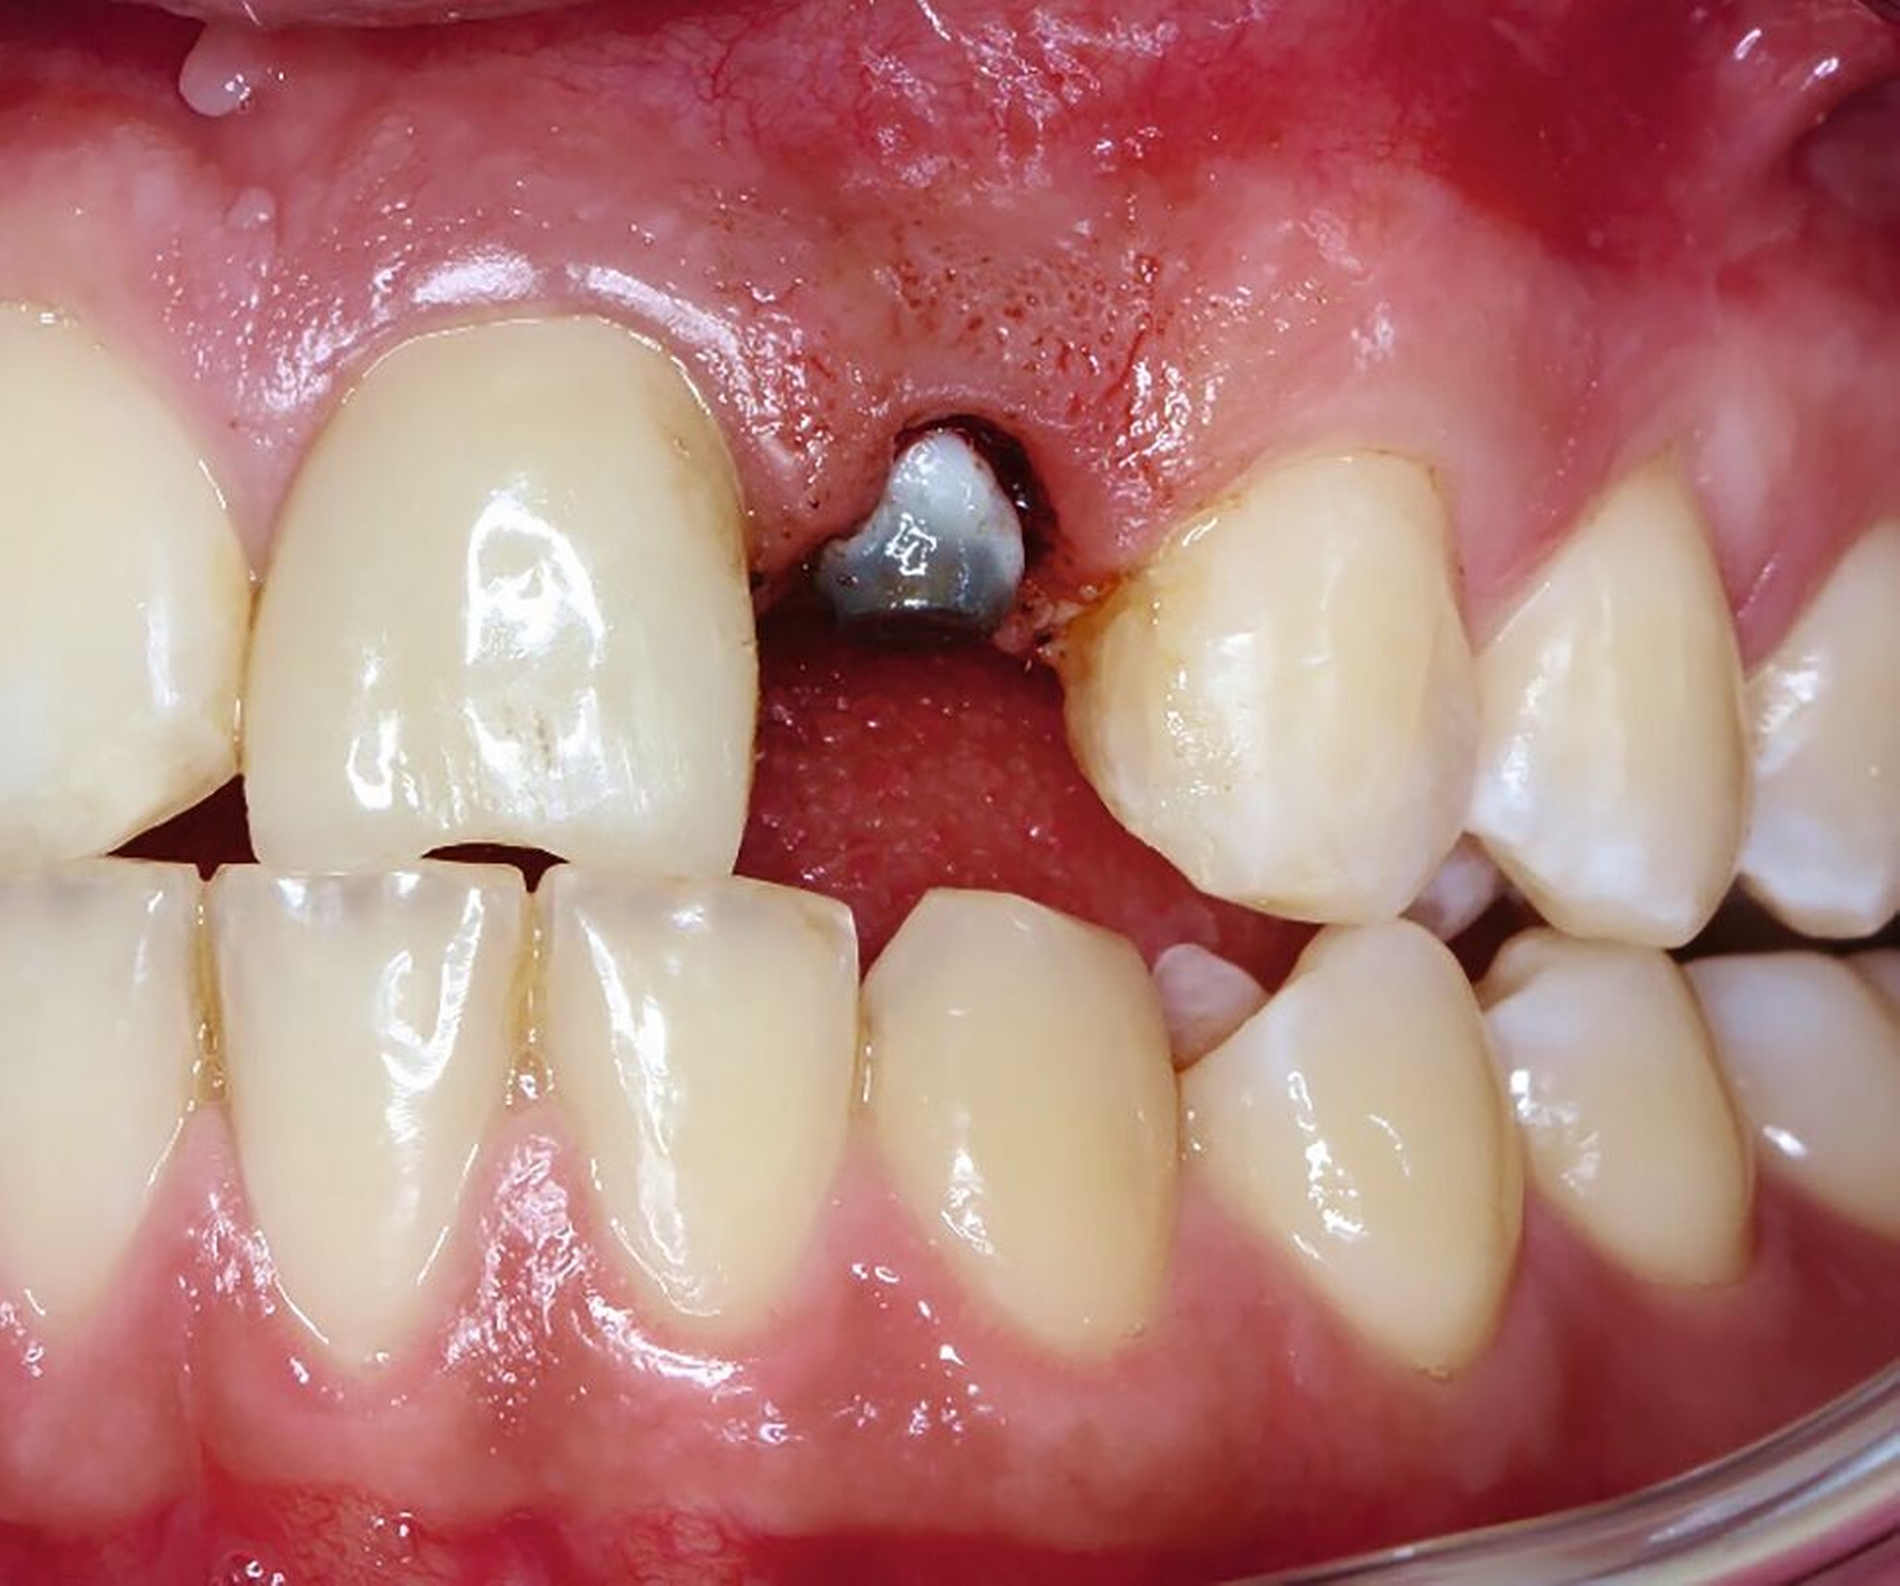

Nachdem eine Wurzelkanalbehandlung durchgeführt worden war, wurde der Magnet adhäsiv befestigt und die Zahnwurzel bis circa 4 mm über das Knochenniveau bewegt. Hierfür waren wochenweise Recalltermine notwendig, um den Magneten in der Schiene umzupositionieren und durch suprakrestale Fibrotomie die parodontalen Fasern zu lösen (Abbildung 22 und 23).

Als die Wurzel des Zahnes 22 ausreichend extrudiert war, wurde ein adhäsiver Stift-Stumpf-Aufbau inseriert (Abbildungen 24 und 25). Die Krone an Zahn 21 wurde entfernt, da diese durch das Trauma inzisal beschädigt worden war und der Patient eine Neuanfertigung wünschte.